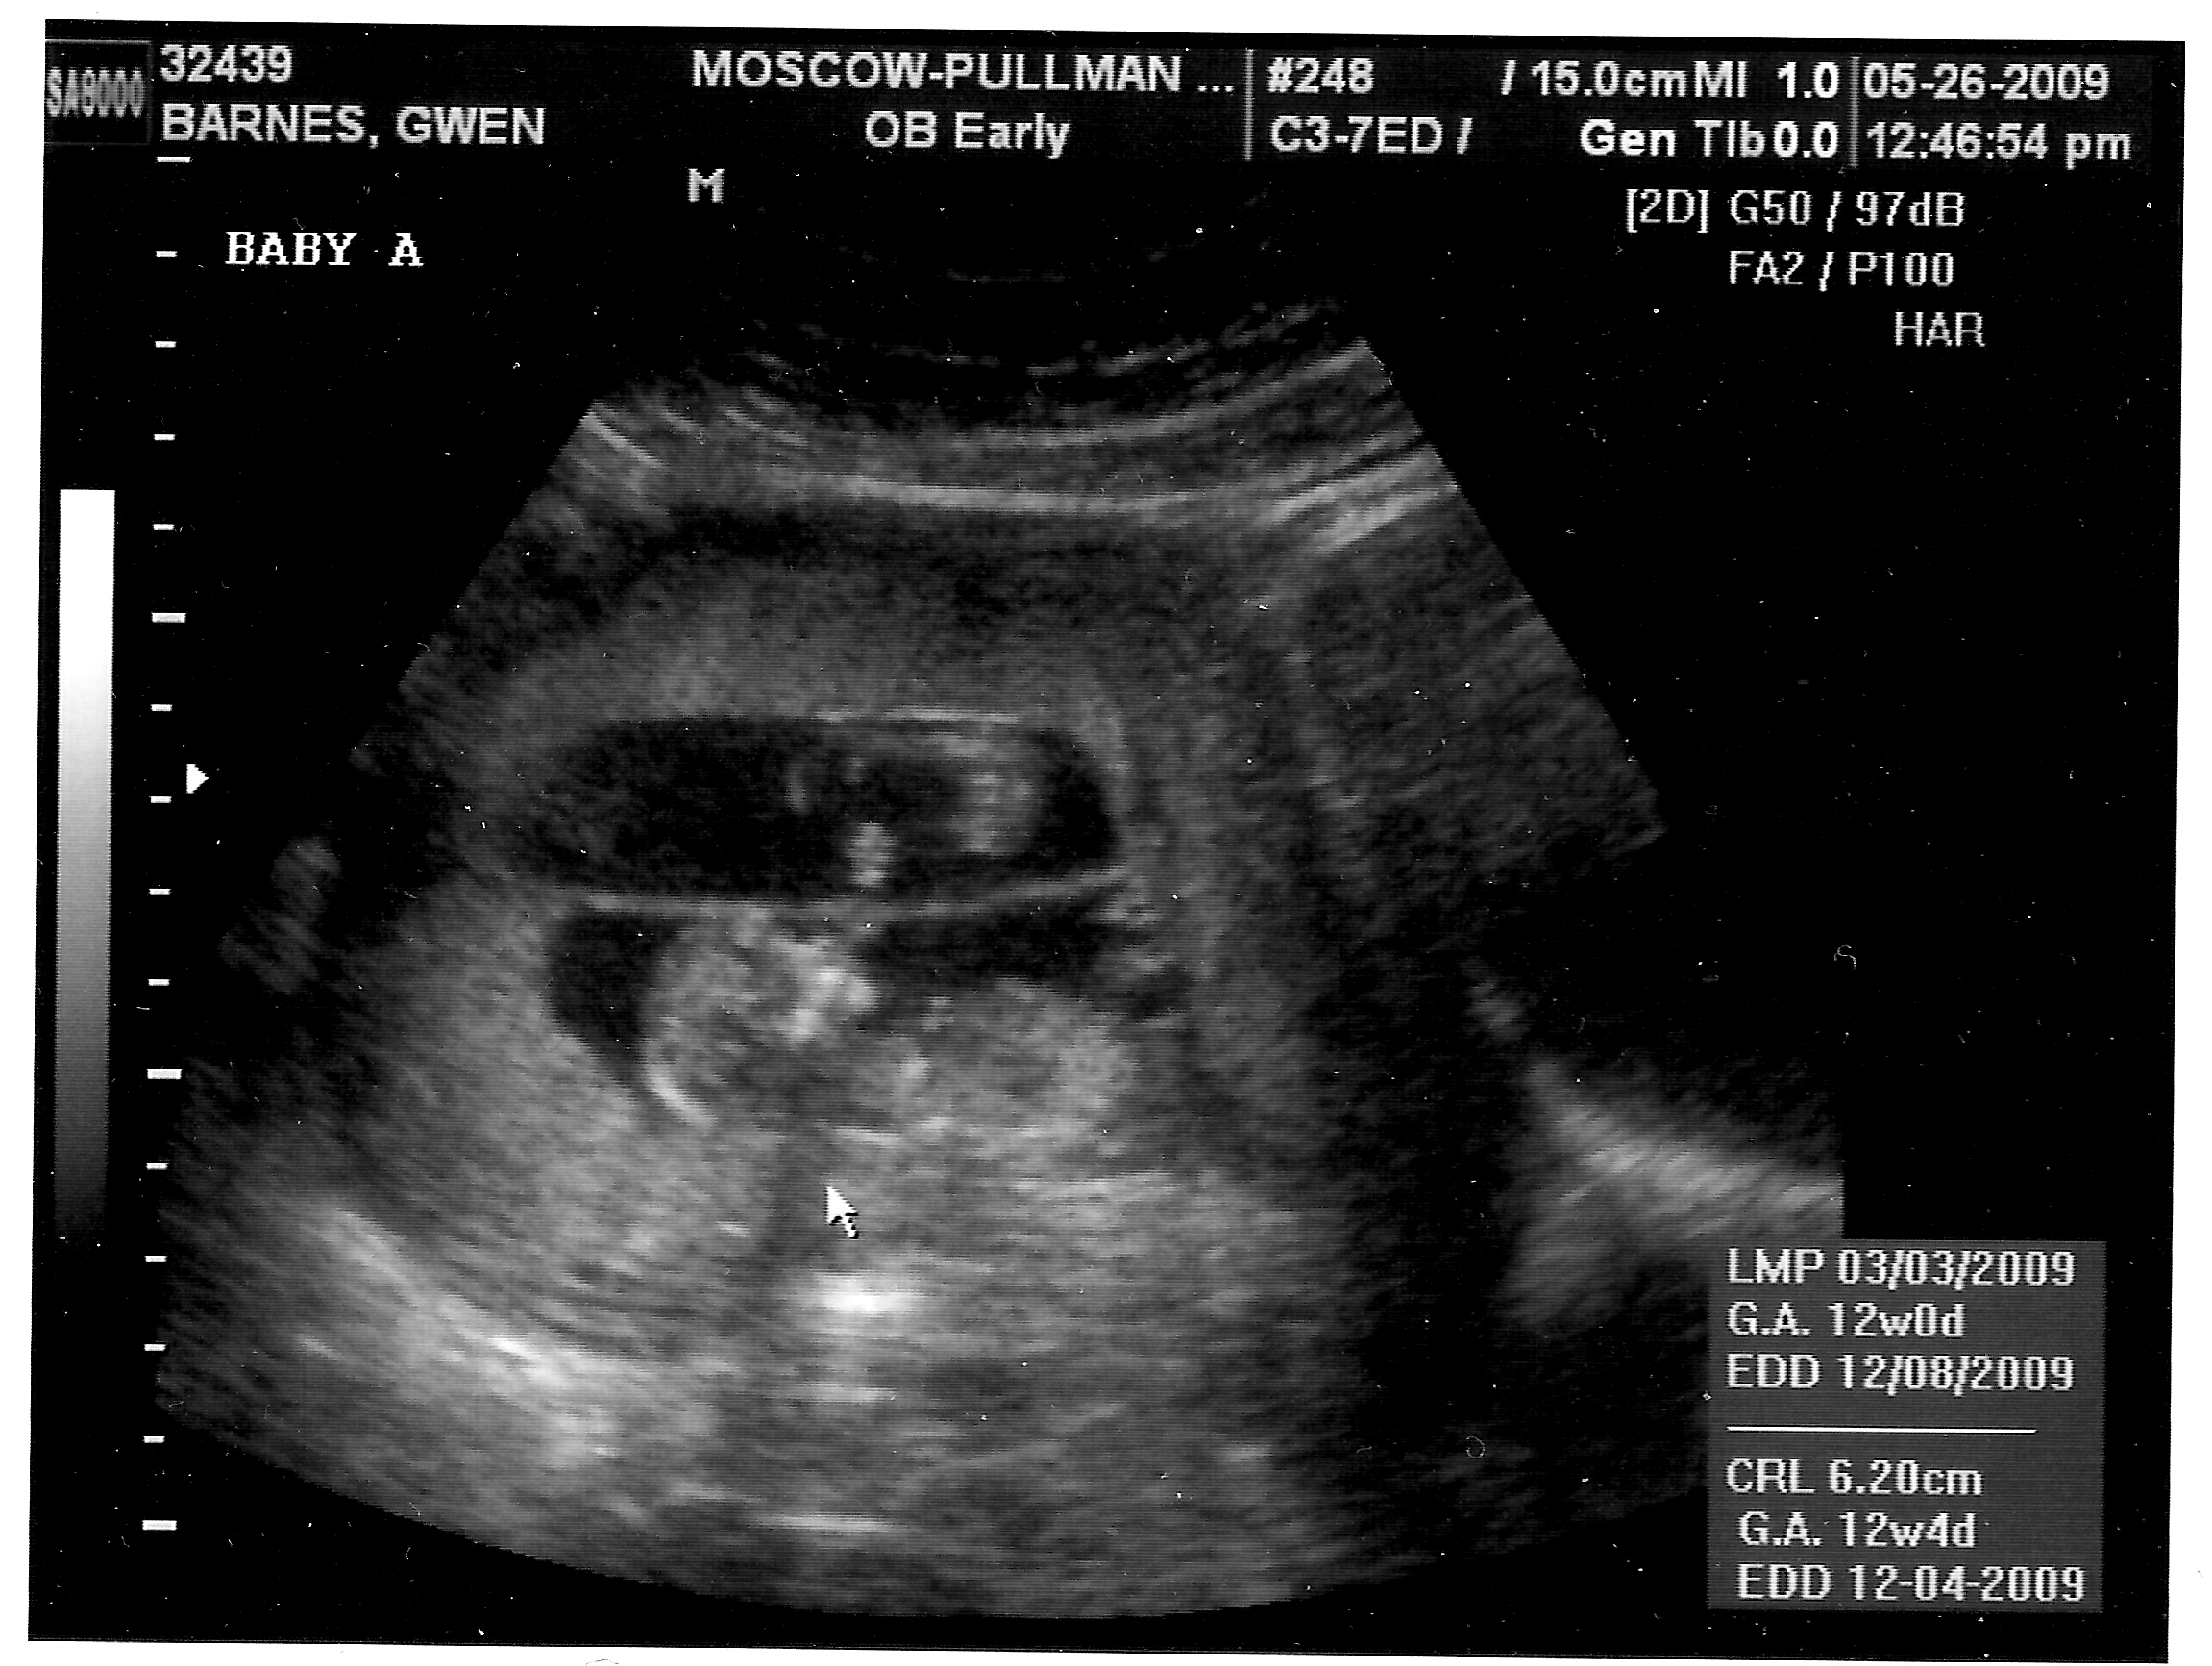

May 26, 2009

Ultrasounds taken on the super-good ultrasound machine by the ultrasound tech in Pullman. This was for the nuchal translucency screening, which came back normal for both babies.